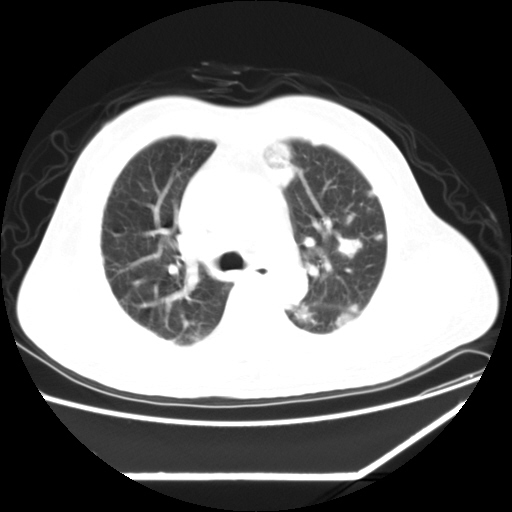

男,57,畏寒,发热

两肺野多发大小不一高密度灶,纵膈内见肿大淋巴结,要考虑转移瘤可能。双侧胸腔少量积液。

双肺多发结节样病灶,部分内见透光区,纵隔内见淋巴结肿大。结核临床如有畏寒,高热,白细胞增高首先考虑迁徙性肺脓肿(多是金黄色葡萄球菌感染)。

注意除外转移瘤。

1)考虑两肺感染性病变(金黄色葡萄球菌肺炎?);建议抗炎治疗后复查排除其他。2)双侧少量胸腔积液。